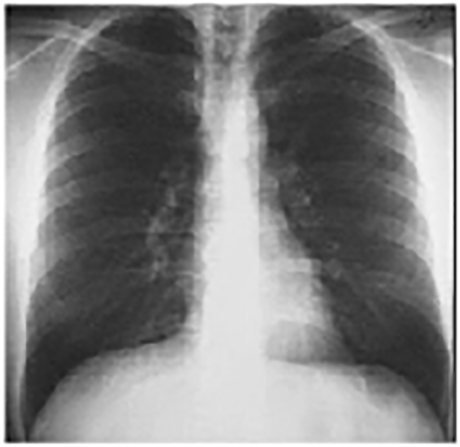

You are incorrect - the best interpretation of the chest X rays in this patient is pericardial calcification

Your choice: Normal PA and Lat

These chest X rays are normal. The pa view demonstrates no abnormalities of the bone structures, lung fields, or cardiac silhouette. The right and left heart borders are normal as are the great vessels superior to the cardiac silhouette. Note the cardiothoracic ratio is also normal, that is, it is less than 50%.

The lateral view is normal, with no evidence of chamber enlargement including the normal anterior shadow of the right ventricle and posteroinferior shadow of the left ventricle.